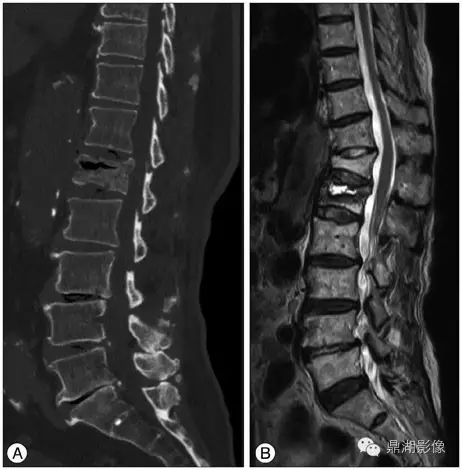

腰椎MRI  T1图像:

T2WI:

MRI:可以有效评估。根据研究发现,MRI 及病理可将 IVC 表现分四型:①液体型,T1WI 低信号、T2WI 散在高信号, 病理学上为广泛的椎体坏死及坏 死后骨吸收;②压缩型,椎体明显楔形变(前柱明显变扁而后 柱无明显变化),T1WI 低信号,T2WI 中等信号,病理上为椎体 坏死、骨髓纤维化、肉芽及反应性新生骨形成;③肉芽组织 型,T1WI 低信号、T2WI 中等信号, 信号分布较压缩型更广且 椎体后部受累及, 病理学为广泛肉芽组织形成;④混合型, MRI 及病理学为前述各型的混合表现。